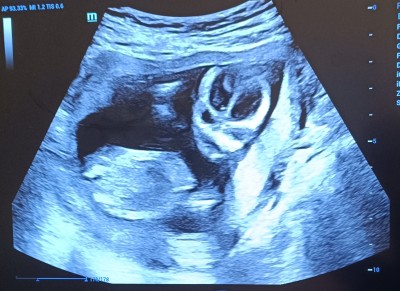

Cinsiyet Tahmini Görseli ile

tahmin?

14+3

Somurtkan bır erkek:))

Haha güldum valla yorumunuza haklisinjz somurtkan sınırlı bir bebeğe benziyor